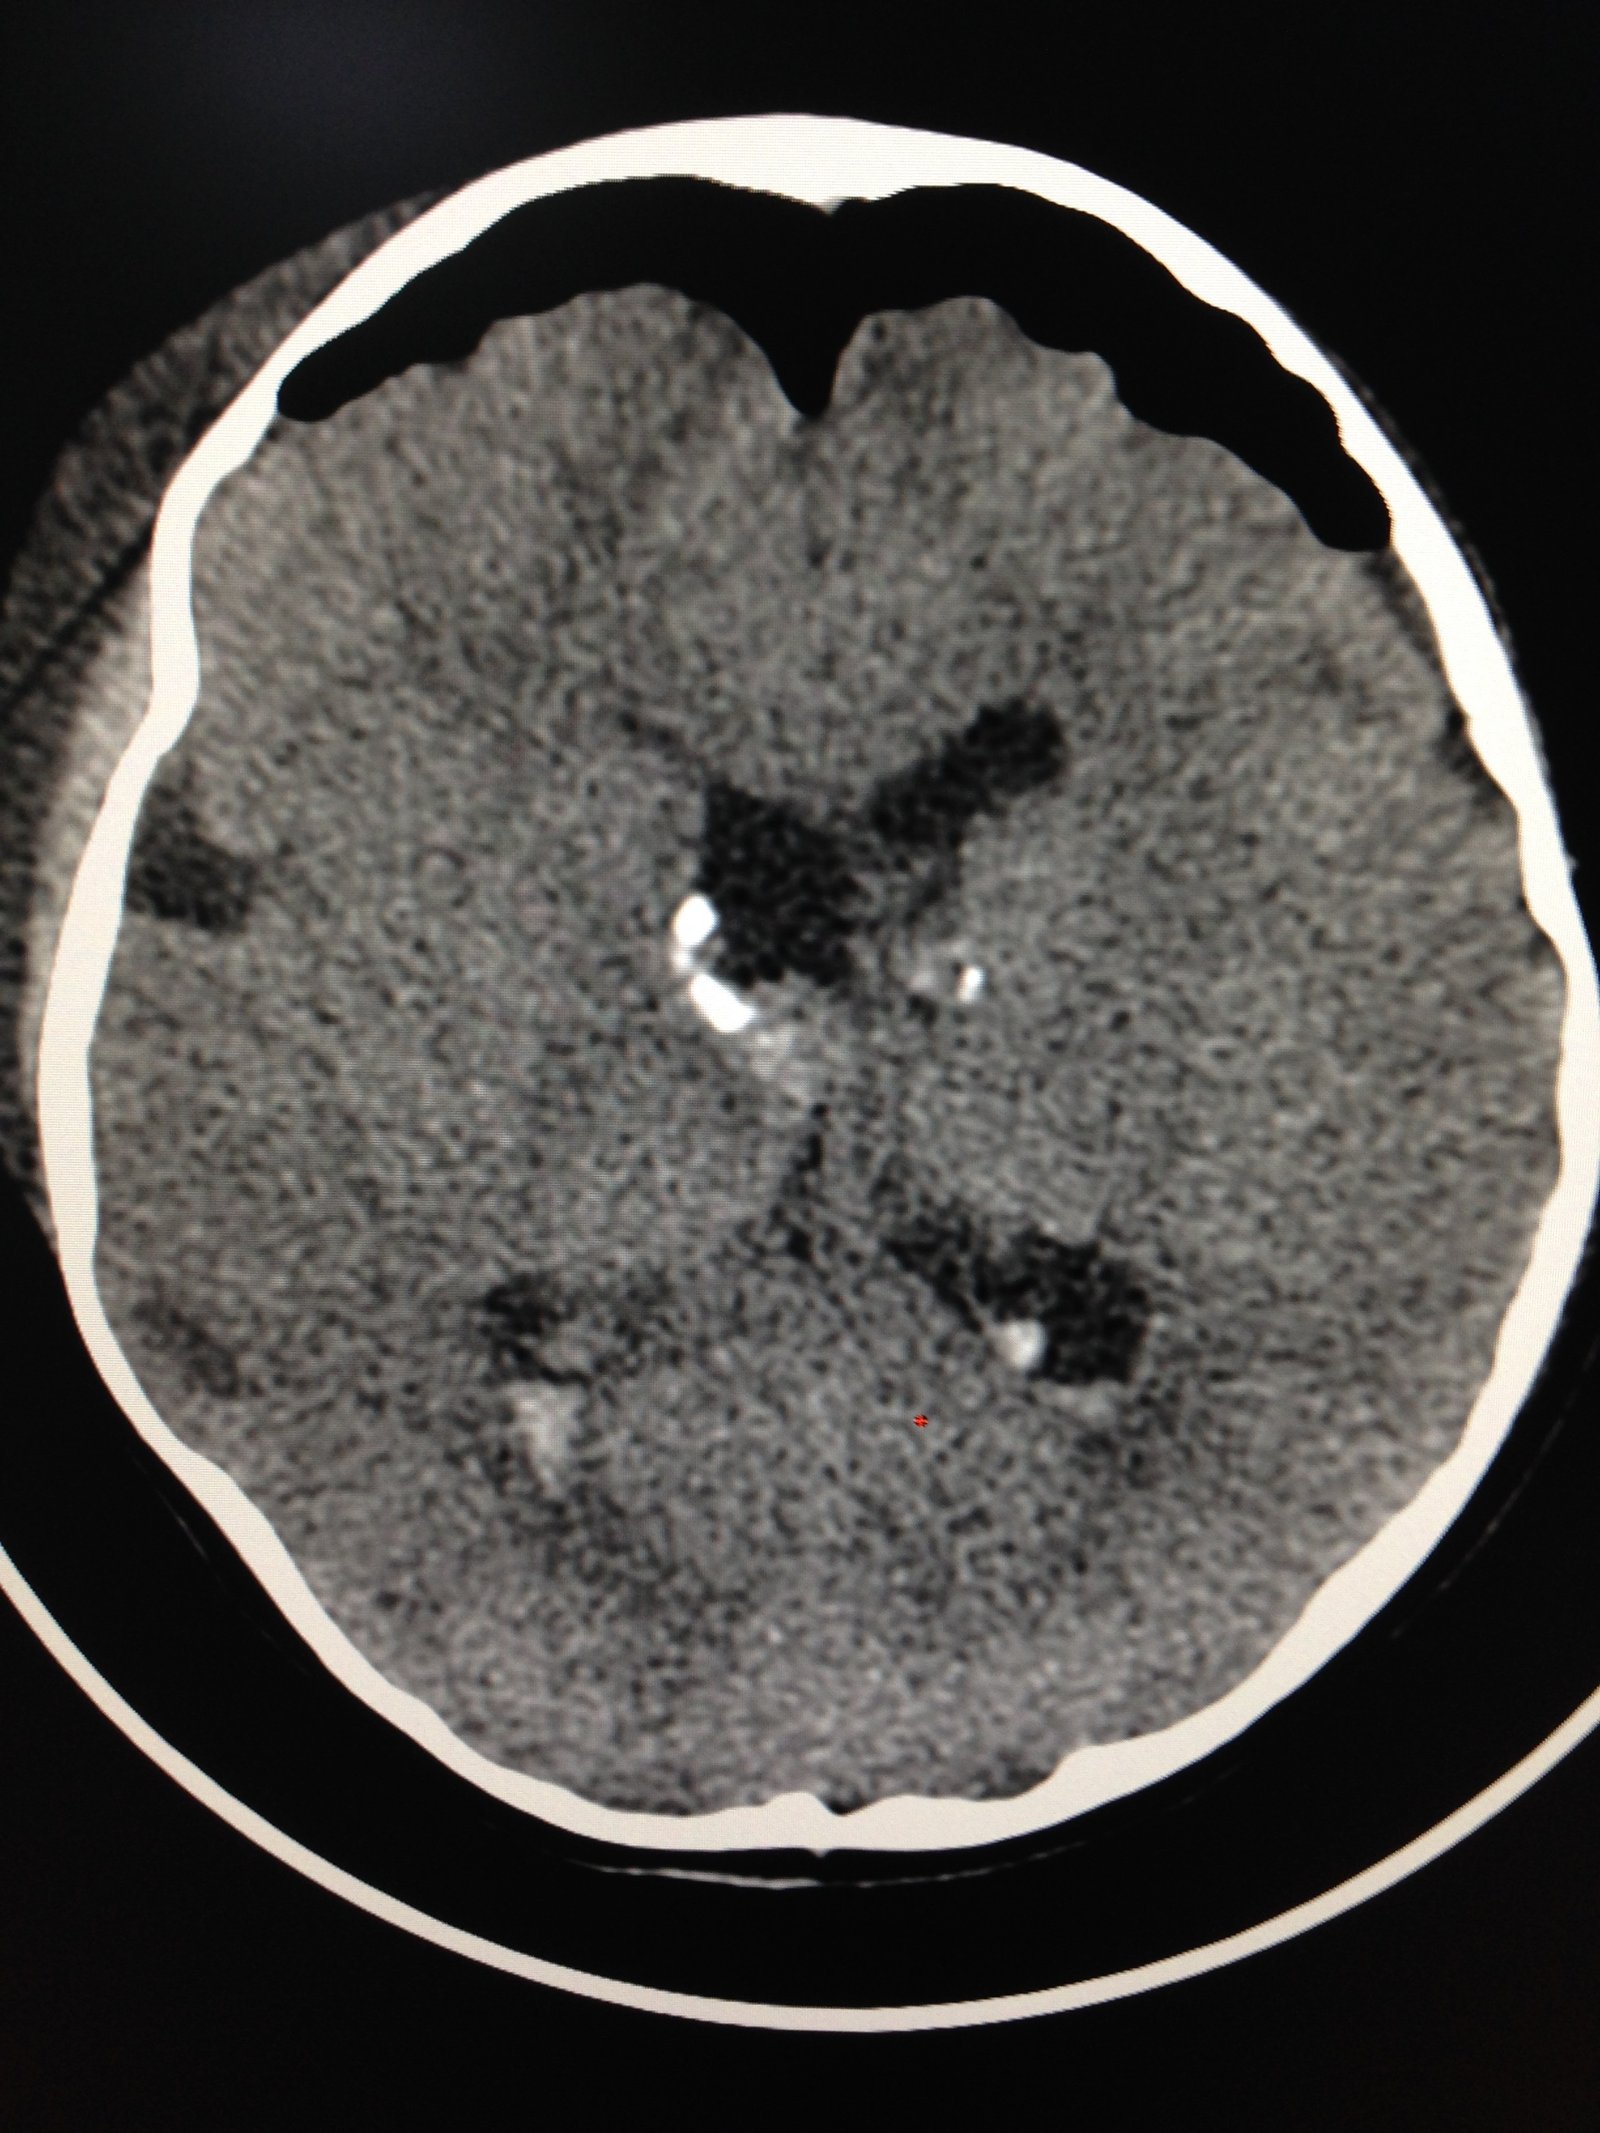

ESCLEROSIS TUBEROSA